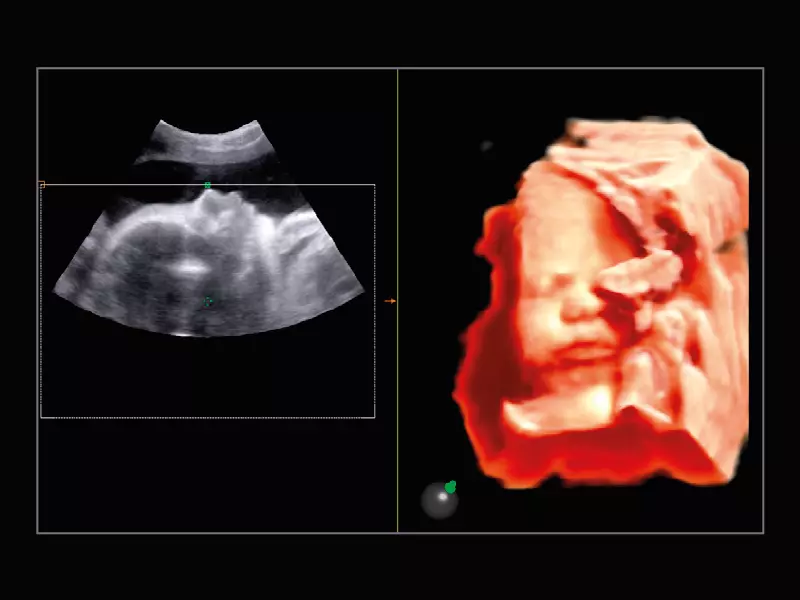

MyLab™E80 - 3D - Baby Face

MyLab™E80 - 3D - Baby Face

MyLab™9 Platform - Real-time baby face with 4D imaging

MyLab™9 Platform - Real-time baby face with 4D imaging

MyLab™9 Platform - Baby Face rendering in real-time with XLight

MyLab™9 Platform - Baby Face rendering in real-time with XLight

MyLab™A70 - Baby face

MyLab™A70 - Baby face

MyLab™C25 - Baby face

MyLab™C25 - Baby face